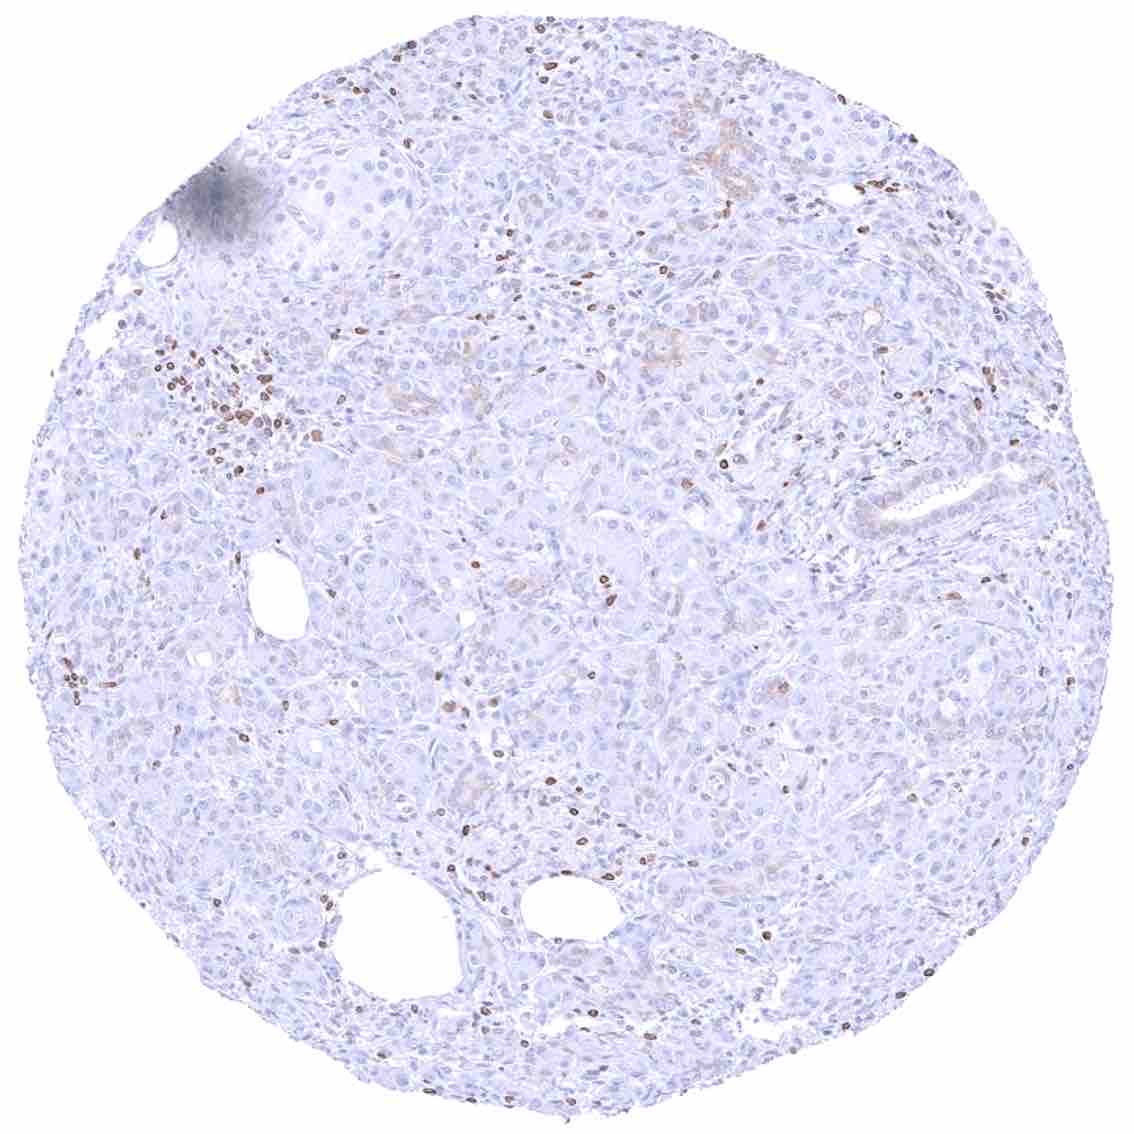

Bone marrow – Only few cells are bcl-2 positive.